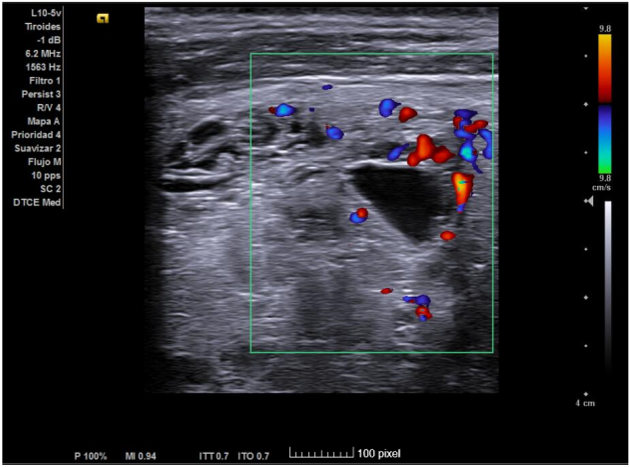

Hallazgos ecográficos

Ecografía clínica de tiroides: Glándula tiroides muy aumentada de tamaño. Istmo irregular de 20 mm. Lóbulos tiroideos desestructurados, aumentados de tamaño (siendo mayor el derecho) y presencia de múltiples nódulos, algunos anecogénicos y otros de estructura espongiforme. No se aprecia aumento de vascularización con modo Doppler que descarta situación de tormenta tiroidea.